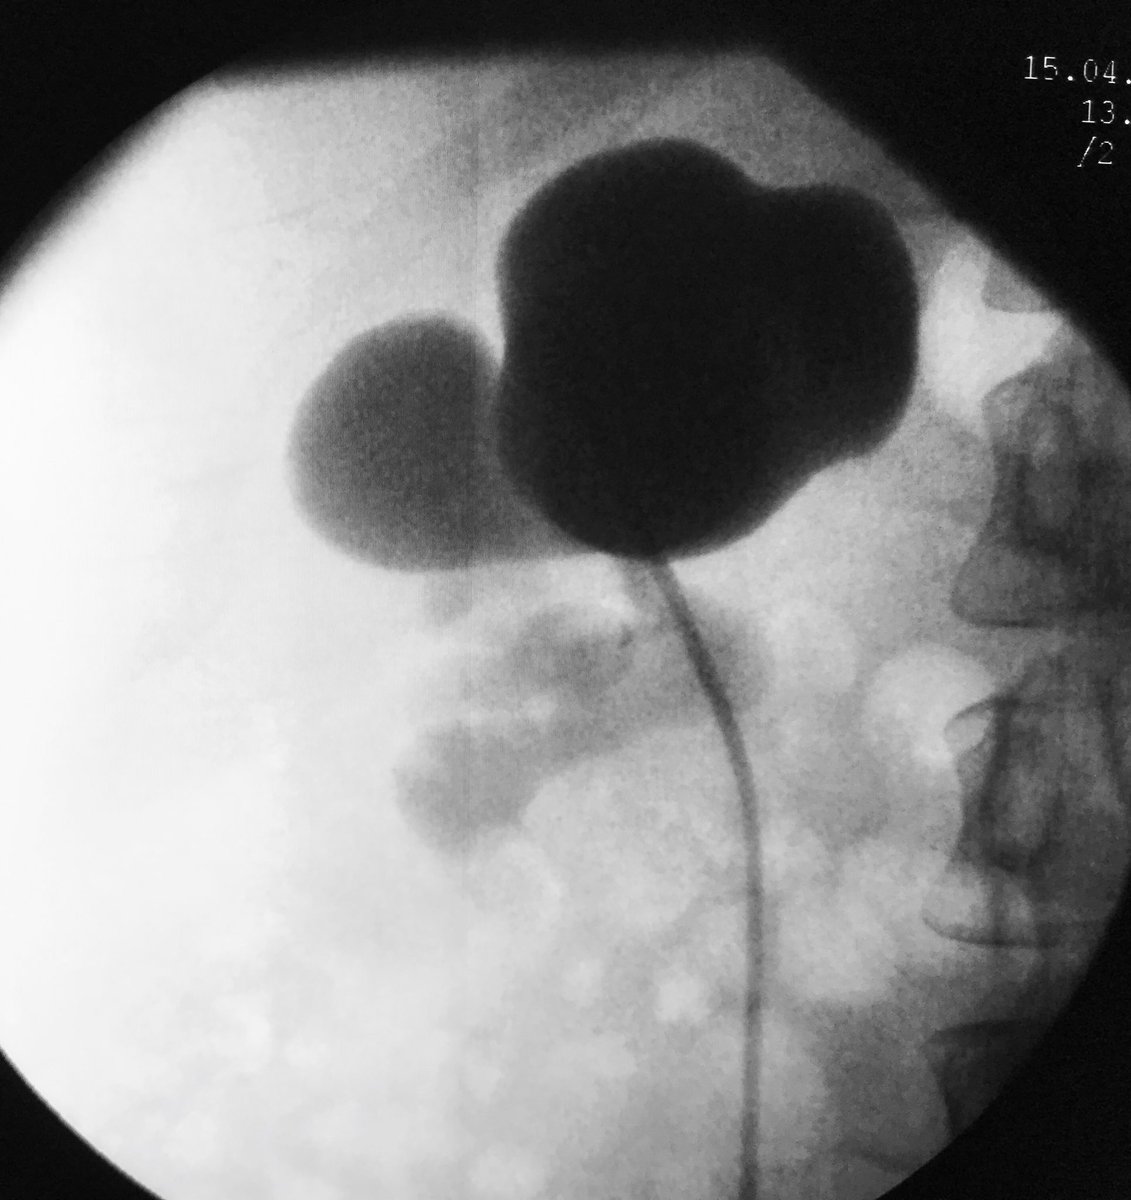

@moeltemamy Excellent surgery!! How do you do the following , (time to set the Jj, time to pyelogram after take off JJ) thanks ) and how do you treat if reestenosis appear ?

PCNL challenges

Eduardo Cruz-Nuricumbo MD Professor endourology